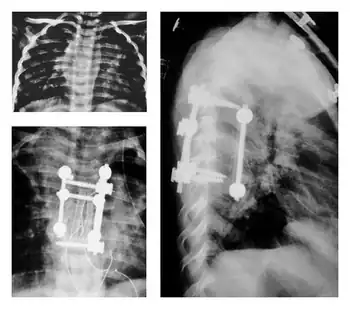

Pediatric surgical interventions

In children with Pott's disease, earlier surgical intervention is often recommended to reduce their increased risk for kyphotic deformity.[1]

This increased risk for deformity is attributed to both the anatomy and biomechanics of children and their developmental stage of life.[1][31]

Due to the proportions of their bodies , limited muscular development, and increased flexibility, gravity can lead to greater deformation and presentation of kyphosis.[31]

After onset of the disease, growth plates in the spine may be destroyed and vertebral bodies suppressed due to kyphosis.[31]

These variable complications would then further deformation, leading to uncontrolled and/or suppressed growth.[31]